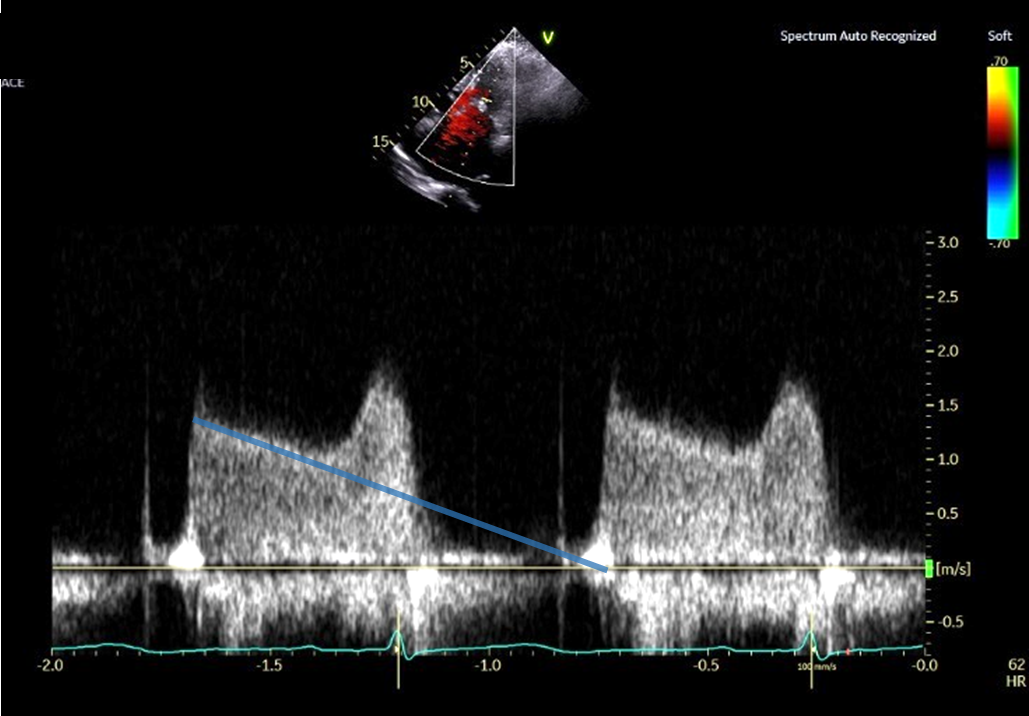

PHT法 拡張早期の急峻な部分を避けて計測した場合 (No15_2)

③ PHT法で弁口面積を求める際は、拡張早期の急峻な部分を避けて計測する